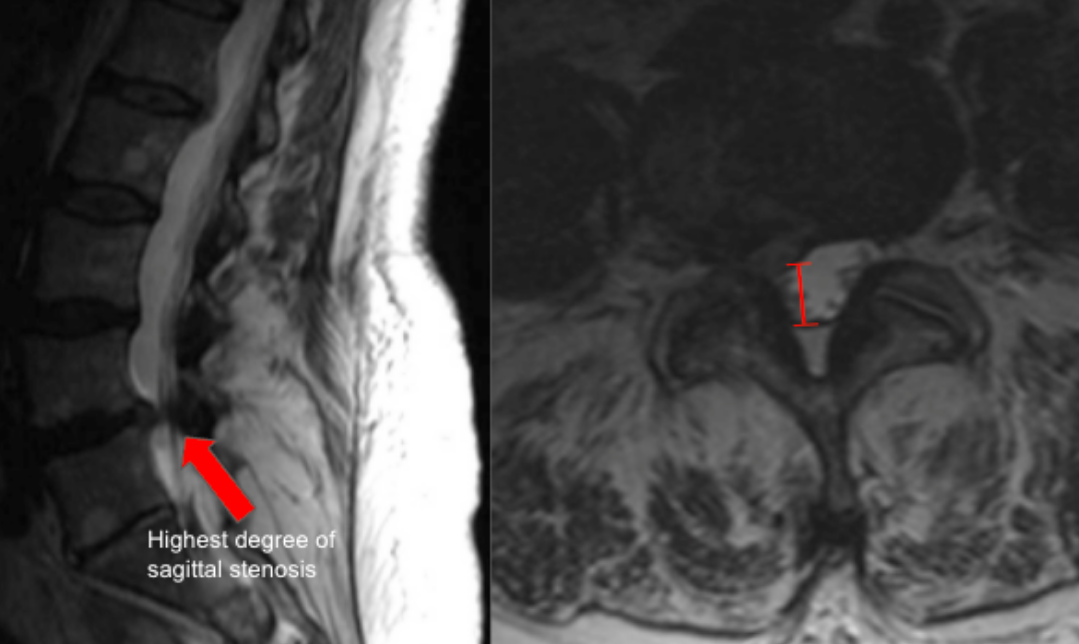

Image Type Lumbar Spine X-Ray CT Scan MRI Scan Anteroposterior (AP) Canal Diameter Cauda Equina Nerve Root Area Conus Medullaris Level Cross-Sectional Area (CSA) of Spinal Canal Disc-Height Index (DHI) Disc Herniation Size Disc Herniation Types Dural Sac CSA Epidural Fat Thickness Filum Terminale Thickness Foraminal Height and Width High-intensity Zone (HIZ) Lateral Recess Width/Depth Modic Endplate Changes (Type I, II, III) Modic (Marrow Signal) Changes Pfirrmann Classification (I-V) Vertebral Bone Quality (VBQ) Score Vertebral Endplate Defects